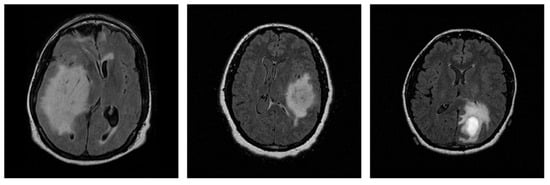

2.1. Data Collection